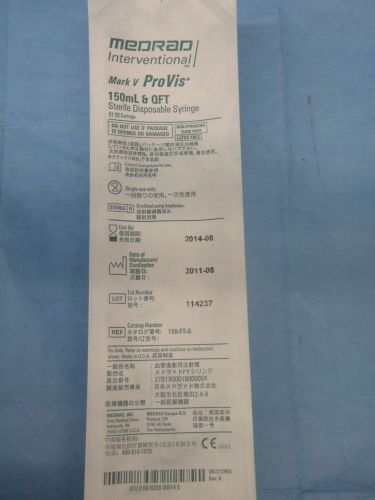

Medrad interventional Sterile Disposable Syringe mark V Pro Vis 150ml